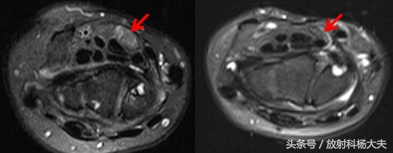

左图为王女士的T2压脂图像,箭头所指为被卡压的正中神经,右图为正常正中神经的图示,对比可见左图正中神经明显增粗。

当出现类似症状时,MRI对腕管综合征的确诊有一定意义,横轴位图像最为典型,可以观察到正中神经的受压扁平,T2WI信号增高或增强扫描出现强化,屈肌支持带弯曲,腕骨和肌腱之间的脂肪间隙消失,和/或正中神经的直径突然改变。其中正中神经形态出现突然变化是最为特征性的变化。